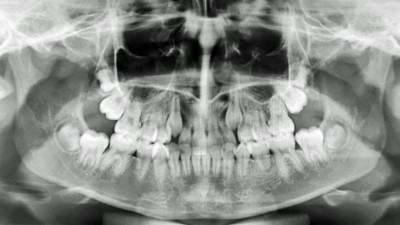

Verlagerte und retinierte Zähne – ein interdisziplinäres Arbeitsfeld

Verlagerte und retinierte Zähne werden in der ersten und noch häufiger in der zweiten Wechselgebissperiode diagnostiziert. Eine frühzeitige Diagnostik kann dazu beitragen, die Eingliederung der Zähne durch eine kombinierte kieferorthopädisch-kieferchirurgische Therapie in die Wege zu leiten. Dieser Fortbildungsbeitrag beschäftigt sich v. a. mit dem fehlenden Durchbruch bleibender Zähne und beschreibt die Zusammenarbeit und das chirurgische Vorgehen bei verlagerten und/oder retinierten Zähnen sowie die Insertion von skelettalen Verankerungssystemen.